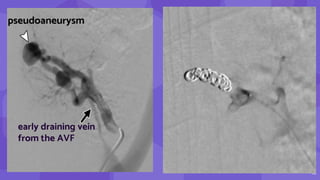

pseudoaneurysm

early draining vein

from the AVF

17

• #17 Image from subtraction angiography shows the pseudoaneurysm (arrowhead) and the early draining vein from the AVF (arrow) Same AVF treated with coil embolization. postprocedure AVFs have been reported in up to 10% of renal allograft biopsies, most of which are asymptomatic with no clinically significant hemodynamic consequences. These cases can be treated conservatively and can be followed up with US as needed, with 70% regressing or resolving spontaneously. Large or symptomatic AVFs resulting in abnormal large or persistent gross hematuria or significant hypertension occur in only 1%–2% of cases and can be treated with catheter embolization